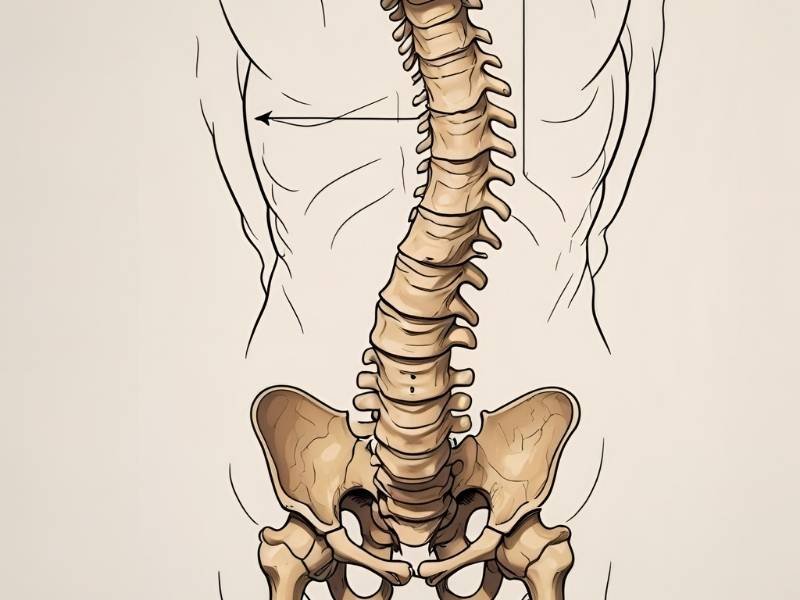

A escoliose idiopática é uma condição caracterizada por uma curvatura lateral anormal da coluna vertebral, sem causa definida. Surge geralmente na infância ou adolescência e pode variar de casos leves até deformidades mais graves que afetam postura, mobilidade e até funções respiratórias.

Tratamento conservador da escoliose idiopática

O tratamento conservador é indicado para casos leves e moderados. Ele busca controlar a progressão da curvatura e melhorar a qualidade de vida sem recorrer à cirurgia. Entre as principais abordagens estão:

Segundo o estudo publicado no European Spine Journal (2025), pacientes tratados de forma conservadora apresentam limitações na correção da deformidade ao longo do tempo, mas sua qualidade de vida (HRQoL) permanece satisfatória. Muitos se adaptam às mudanças físicas e conseguem manter boa funcionalidade mesmo com algum grau de progressão da curva.